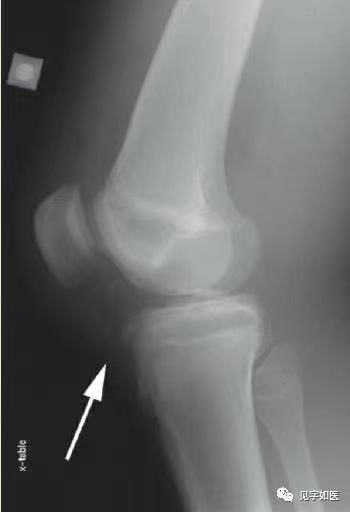

副髌骨骨折:局部无明显压痛,伸膝无明显受限;X线片见骨块边缘整齐、光滑,多对称存在,多发生在髌骨的外上角。